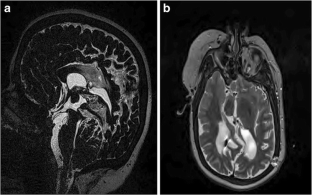

Fig. 1